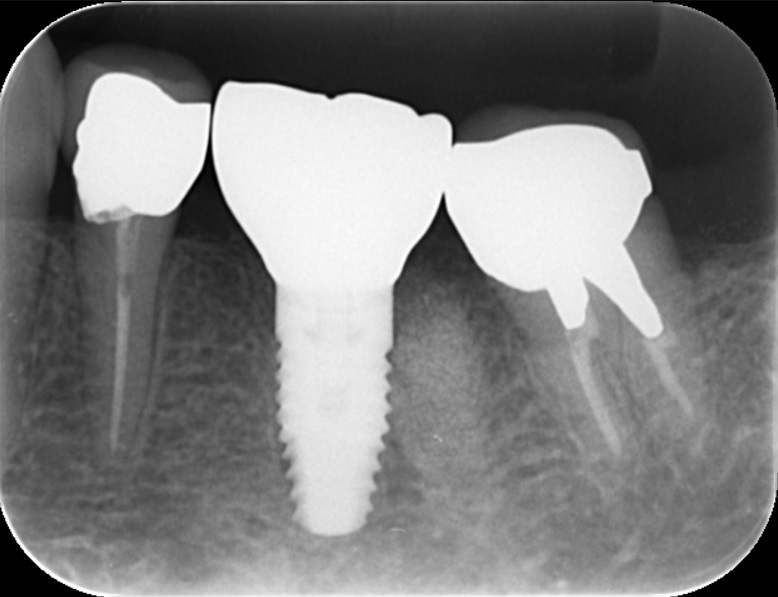

| カウンセリング | 奥歯は歯根破折をおこしていたため保存不可能な状態でした。 |

| 治療内容 | 隣在歯が健康な歯であったため、ブリッジではなくインプラント治療を選択されました。治療期間を短縮するため抜歯と同時に骨再生、インプラント埋入を行いました。型取りは高精度の口腔内スキャナーを用いてデジタルで行い、精密なセラミック修復を行いました。 術後の経過は良好で、短期間で歯が蘇り満足していただけました。 |